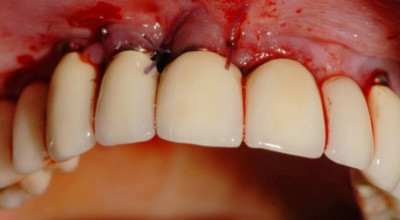

Im Rahmen der Initialbehandlung (drei Termine innerhalb einer Woche) wurden die periimplantären Taschen mit CHX gespült sowie eine Reinigung der denudierten Implantatoberflächen mit dem Vektor unter antibiotischer Abschirmung (Amoxicillin 1000 3x1 pro Tag) durchgeführt und unmittelbar danach mit dem ­Diodenlaser die Innenseite der Taschen deepithelisiert (Abb. 3). In der darauffolgenden Woche schloss sich der operativ-regenerative Eingriff an.